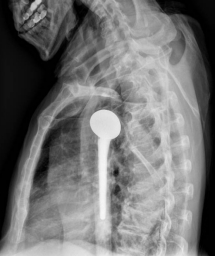

术前X线片